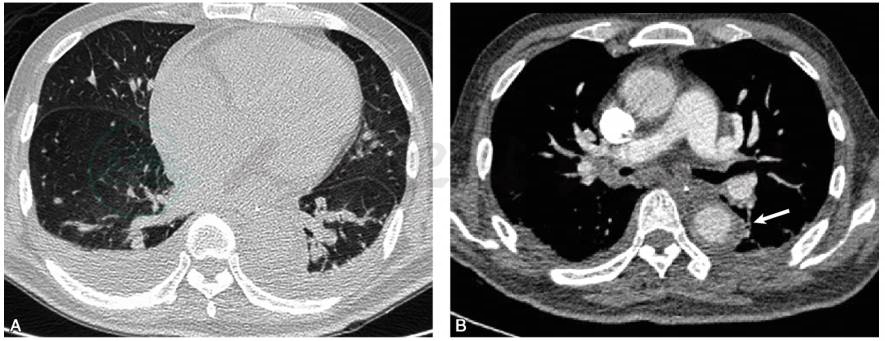

肺动脉CTA(2017-02-22,外院报告):双侧肺动脉主干末端显示不清,考虑肺栓塞可能大,请结合临床随访。附见胸腔积液,左下肺膨胀不全(图1)。

图1 肺动脉CTA

A.肺窗示双侧肺野清晰,心胸比例增大,双侧胸腔积液并左下肺膨胀不全;B.纵隔窗示胸主动脉管壁显著增厚,管腔不规则(白箭)

患者卧床时间较长,病程中曾有发热伴多痰,痰培养发现鲍曼不动杆菌,经抗感染治疗后,症状有所改善。2017年2月22日肺动脉CTA肺窗示:双侧肺野清晰,心胸比例增大,双侧胸腔积液并左下肺膨胀不全;纵隔窗示胸主动脉管壁显著增厚,管腔不规则;近端肺血管未见明显充盈缺损,段以下肺血管显影欠佳。外院给予治疗剂量的低分子肝素抗凝,患者胸闷症状无明显改善。综上所述,患者肺栓塞可能性不大,有可能是系统性血管炎导致胸闷、低热与胸腔积液的表现。